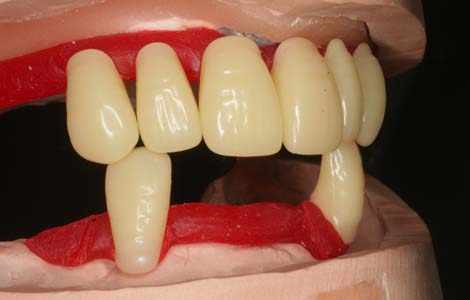

歯を1個1個並べていく

人工歯は、1本1本並べていきます。既に歯は無くなっていますので、お口の中の形からどこに並べるかを想像するしかありません。とても重要な作業もあり、非常に難しい作業でもあります。10人の歯科医がいれば10通りの歯並びができるといっても過言ではありません。

噛み合わせ・審美性・話しやすさ

すべてに配慮

人工歯を並べる位置は患者さんごとに異なります。そのため、人工歯は1本ずつ分かれていて、自由に配置できるようになっているのです。術者の知識と技術がもっとも必要とされる作業です。患者さんに満足して頂ける入れ歯を作るには(1)噛み合わせ (2)審美性 (3)話しやすさをすべて満たさなければなりません。これらを総合的に配慮しながら入れ歯を作ることで、より元の歯に近い噛み心地を提供できるのです。

写真は発音の検査をしているところです。入れ歯の形は、食べ物の流れをコントロールしたり発声時の音を作るのにもとても影響を及ぼします。ですから、一見何の変哲もなさそうなピンクの部分も、より快適な入れ歯を作るためには非常に重要な役割を担っています。こうした細部のこだわりがピッタリの入れ歯作りに必要な作業なのです。